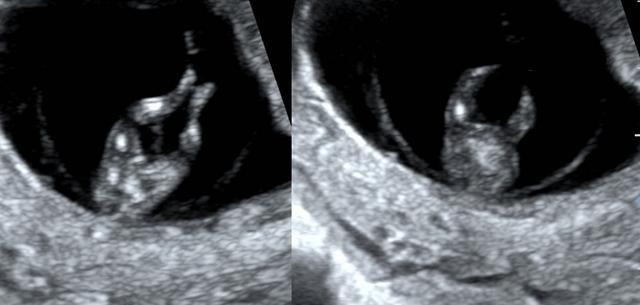

当然,这个时期我们除了重点观察TA的肢体以外,此时需要重点关注NT。

NT测量一般在11-13+6周内进行。

此时测量彩具有参考意义,但测量NT完全看宝宝的心情。

因为TA 有时候真的很不给面子。。。

比如:

有这样趴着的;

还有倒立的